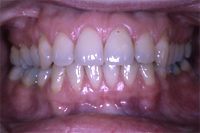

Die Abb. 1 bis 4 sollen als anschauliche Beispiele für gesunde und kranke Fundamente dienen.

Ein 31 Jahre alter Patient zeigt einen starke Zahnfleisch-Rückgang im Oberkiefer (Abb. 1 und 3) und wir beschliessen, diese Rezessionen zu behandeln.

Der Erfolg der Behandlung ist deutlich in den Abb. 2 und 4 zu sehen. Sehr augenfällig konnte die Situation um den Eckzahn im linken Oberkiefer verbessert werden (vergleiche dazu Abb. 3 vorher und Abb. 4 nachher).